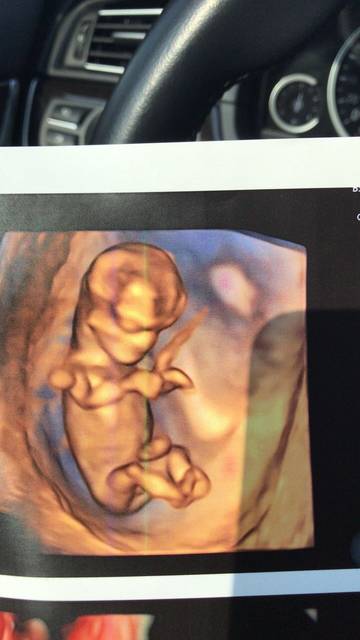

三个月建档归来,新出nt看得出弟弟妹妹么?_怀孕1-3月圈 - 妈妈网

nt图能看到小孩五官吗?_NT照片,图1里是眼睛鼻子嘴吗?不_宝宝树

nt图这样是不是就是儿子了